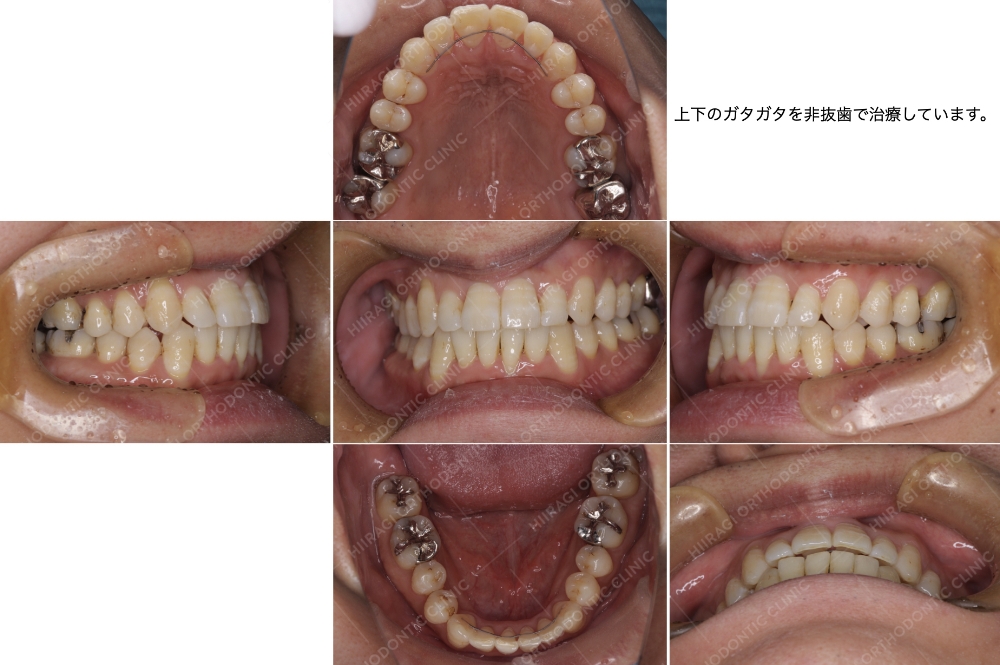

| 主訴 | ガタガタがあり歯が磨きにくい。 |

| 抜歯 | なし |

| 治療期間 | 3年4ヶ月 |

| 性別 | 男性 |

| 年齢 | 29 歳 |

装置:唇側矯正装置(インシグニア)